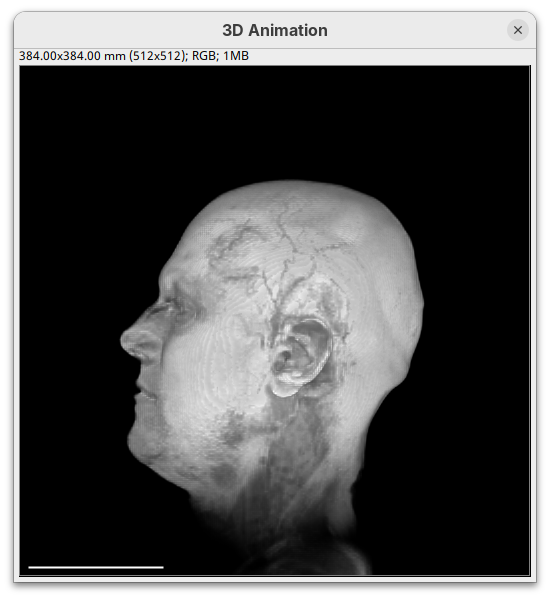

3D Project

This is a simple tool to quickly generate a 3D animation (e.g., 360-degree rotation) from an image stack. There are basic parameters for adjusting the rendering, like projection method and opacity, and for controlling the animation. There’s only a bit of documentation. To try:

- Go to

Image>Stacks>3D Project...and clickOKto generate a basic animation.

As noticeable above, 3D Project doesn’t do so well with our MRI dataset. However, it works OK for fluorescent microscopy images, so I encourage you to try with other datasets in the future.